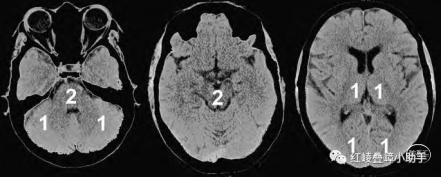

2.后循环ASPECT评分

后循环的ASPECTS(pc-ASPECTS)将后循环分为10分;

左、右丘脑,小脑和大脑后动脉的每一区域分别减1分;

中脑或桥脑任何区域减2分。

定义为CT上的低密度灶或灰白质模糊区相应的血管成像低密度区评分。